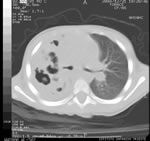

Siamo all'11° giorno di ricovero. Sempre febbre (39-40°C); la PCR era in ulteriore calo: 1,7 (poi rialzo a 2,5). Si decide di eseguire la TAC del torace con l'ipotesi che possa avere o un ascesso o un'altra complicanza.

La TAC del torace (Figura 4) mostra un esteso addensamento polmonare disomogeneo per la presenza di multiple aree ipodense e necrotiche nel cui contesto si apprezzano numerose cavità a contenuto aereo (pneumatoceli).

Opacità al campo superiore medio di dx con area di relativa radiotrasparenza nei settori più craniali, da possibile iniziale cavitazione. Figura 4